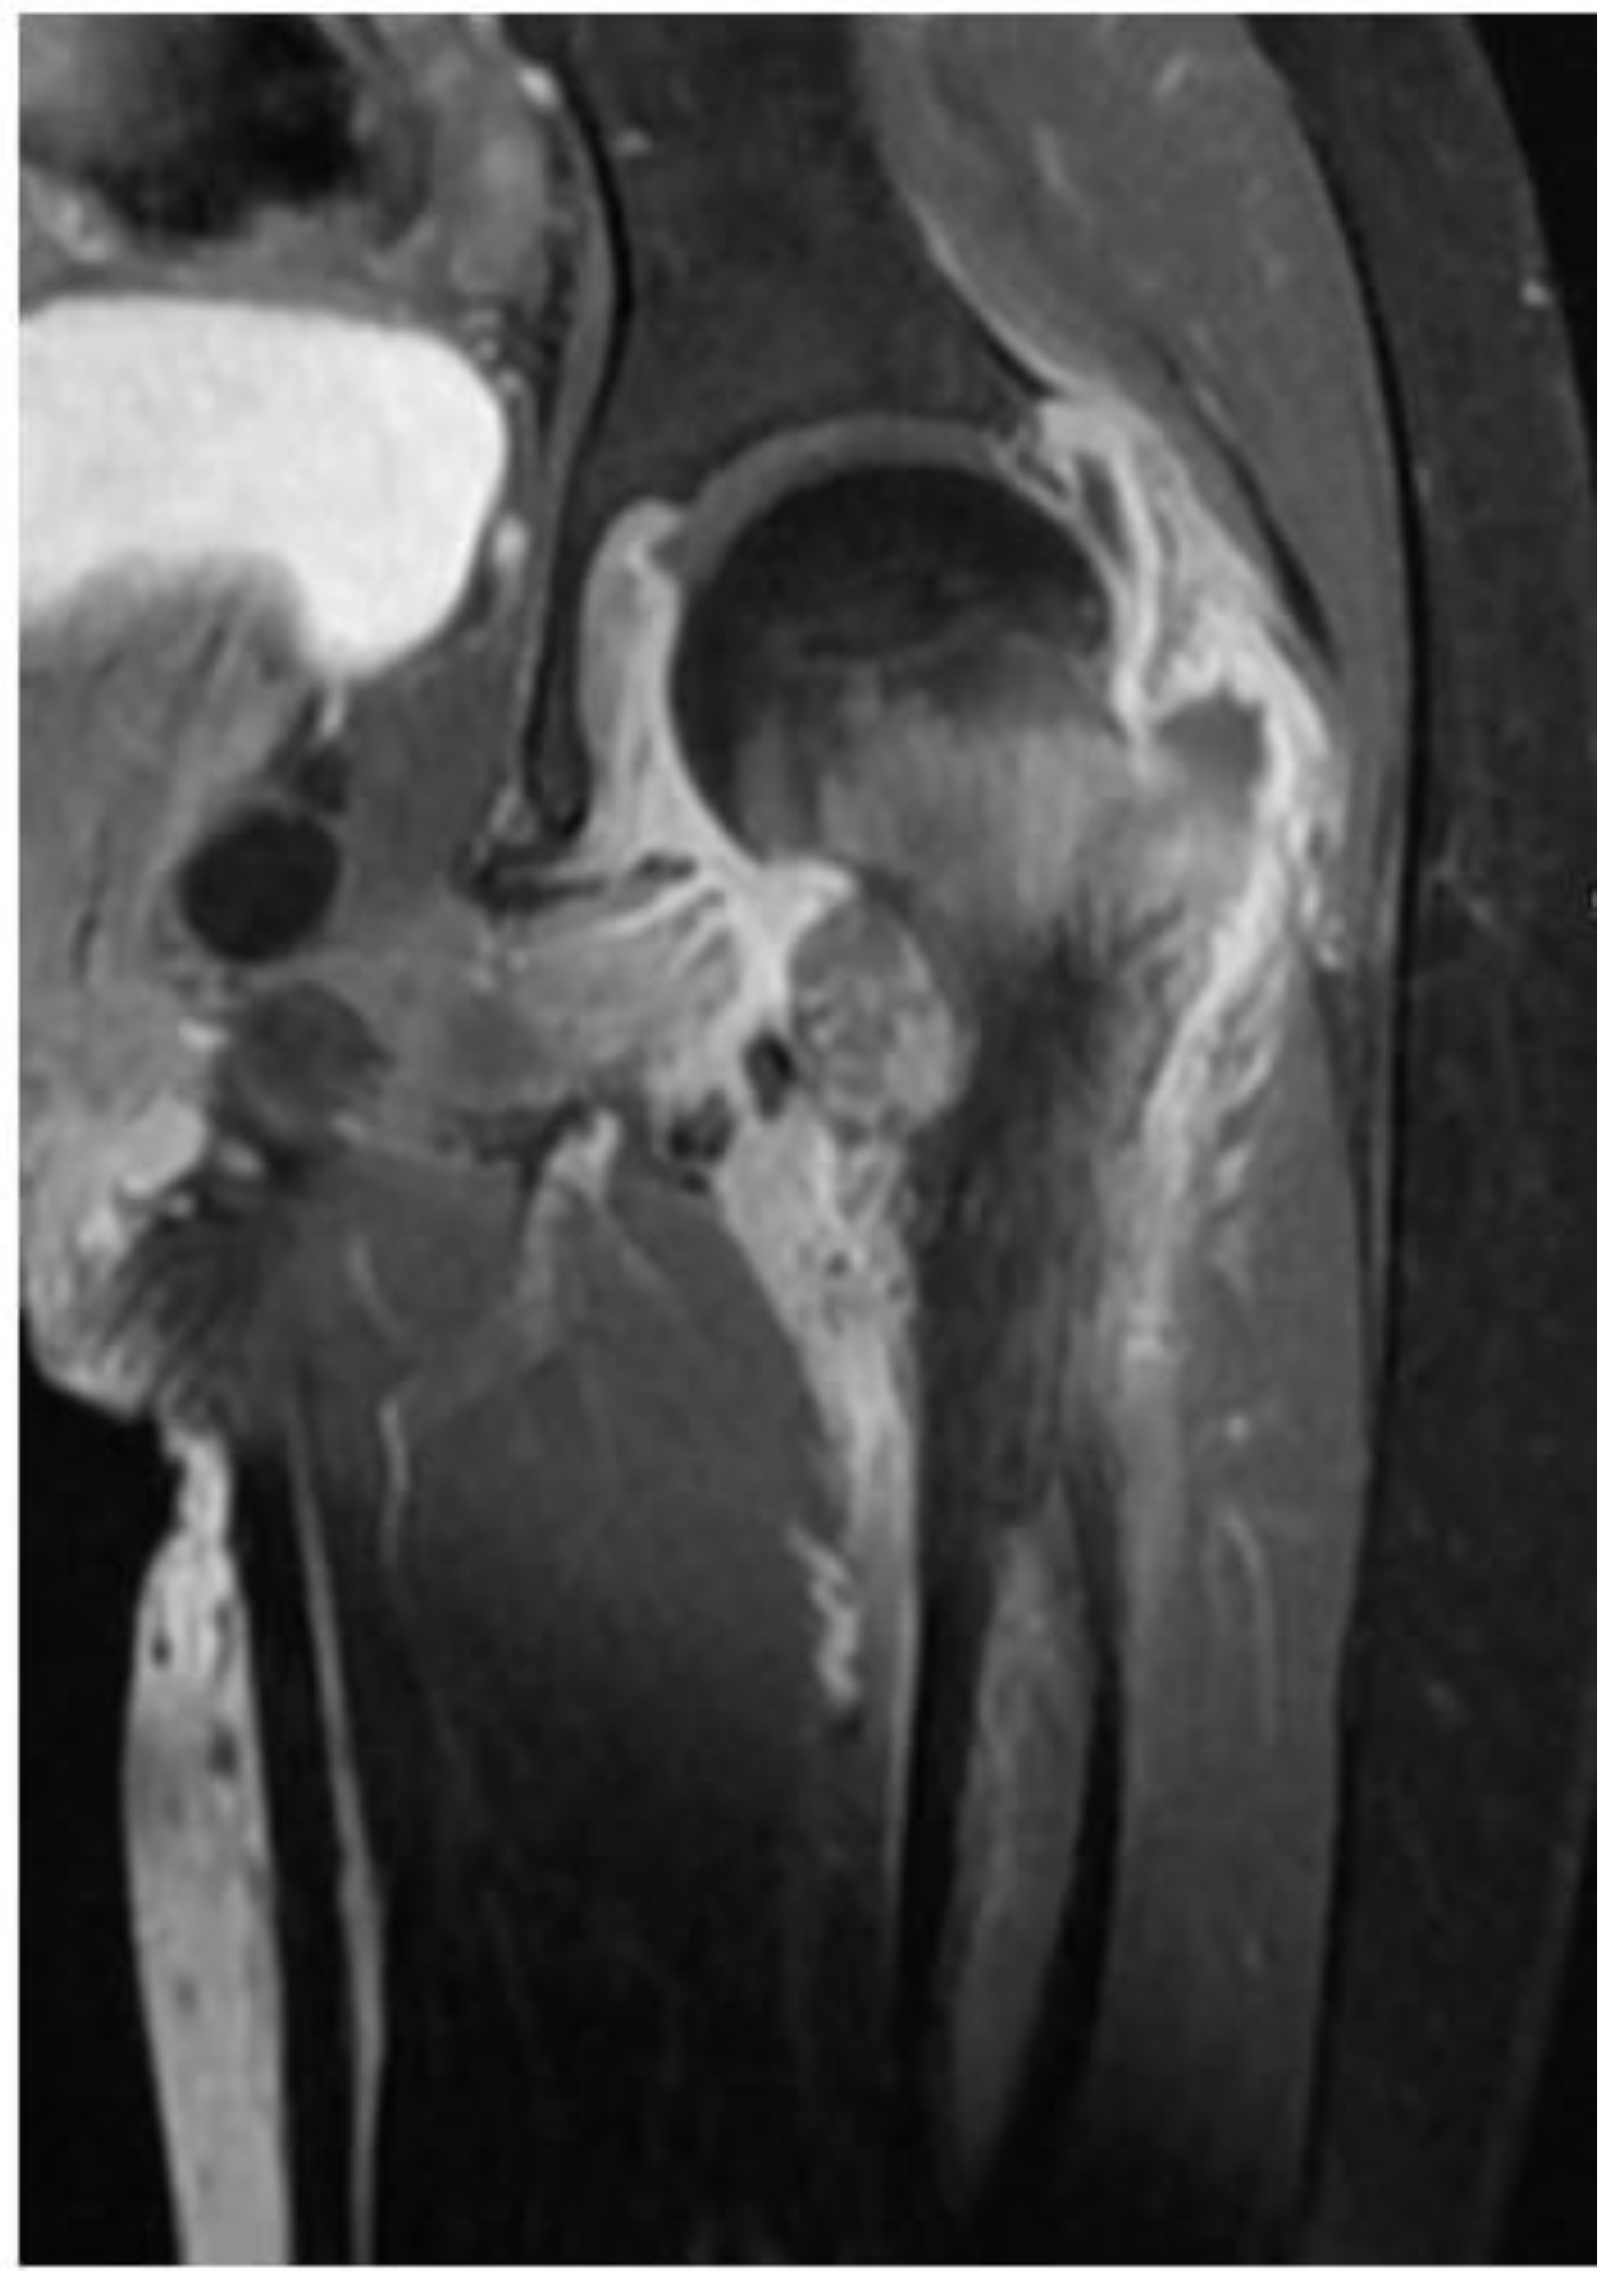

2. Case

| Index case | 12Y/F | Healthy child | Chronic osteomyelitis | Tissue culture | P. species | VRC total 6 months with surgical debridement | Resolution |